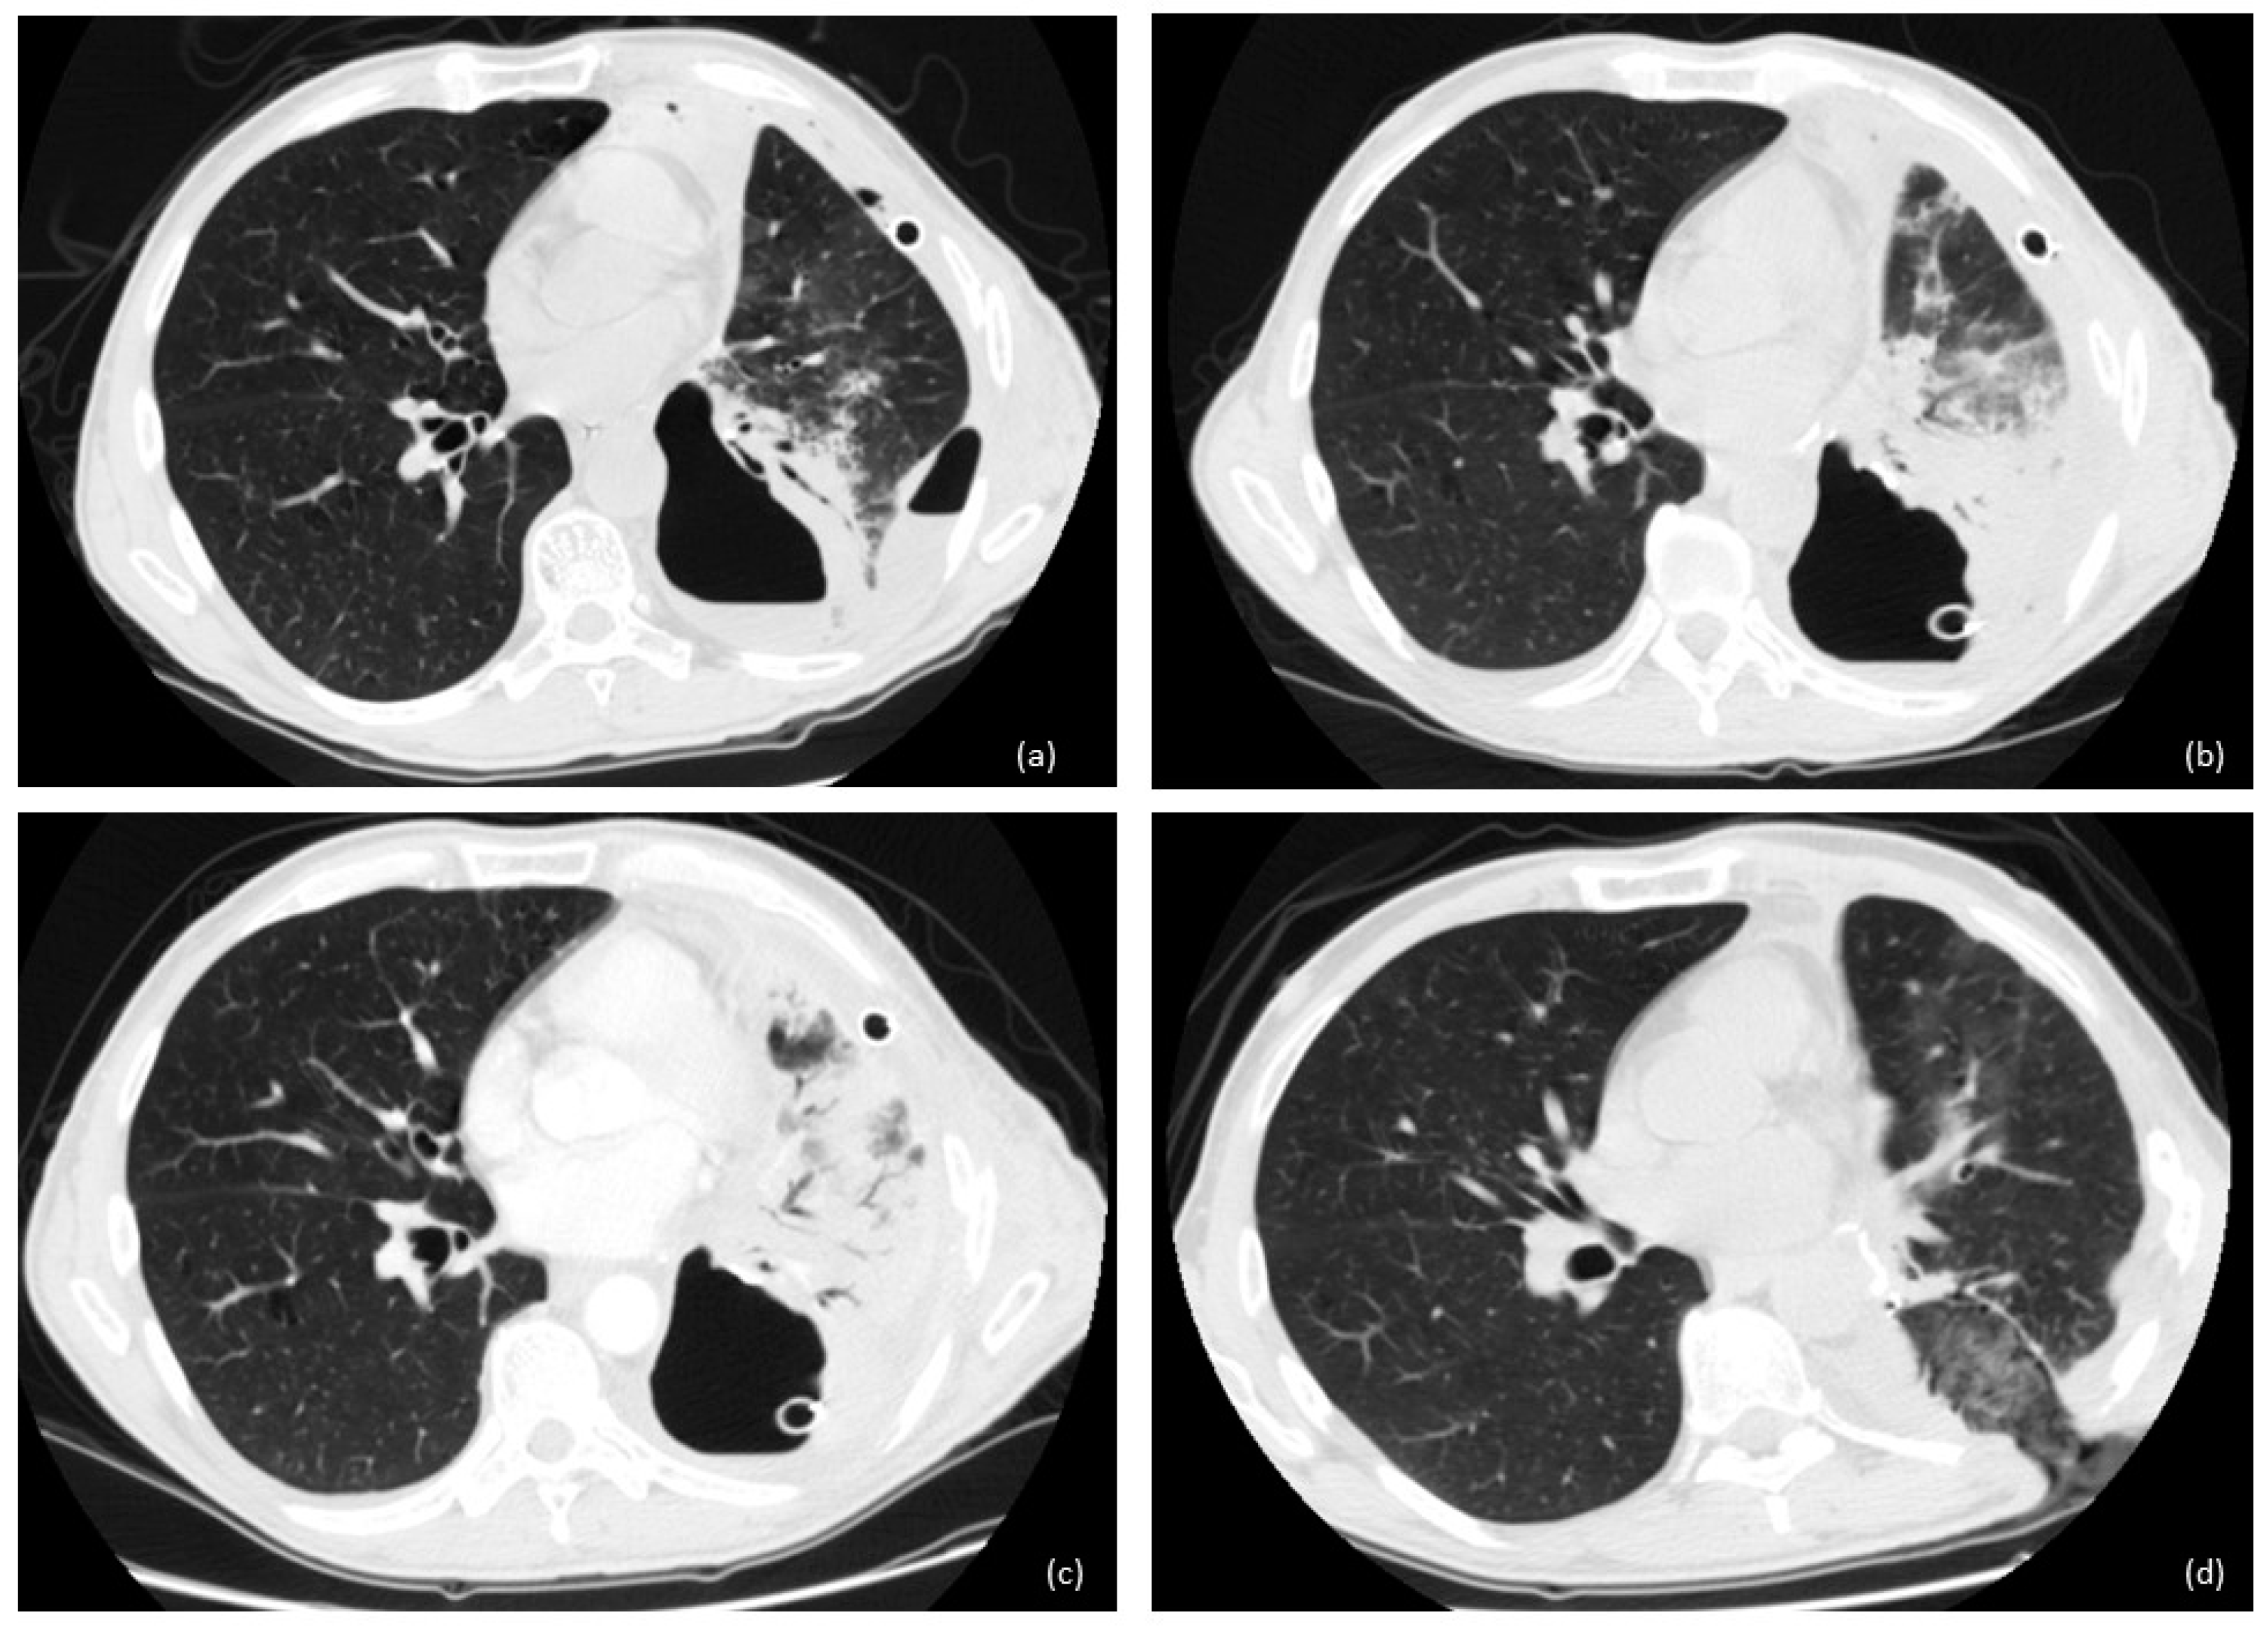

In the case of an unfit patient, small fistula, or small size of fluid–air collection, we opted for open window thoracostomy (OWT) (Figure 2 and Figure 3). The surgical technique of OWT has been widely discussed in our other papers [2,3].

Figure 2.

Evolution of BPF after left lower lobectomy: (a) empyema; (b,c) chest tube with no improvement on BPF with pneumonia of remaining lung; (d) open window thoracostomy with 2 gauzes in the cavity and resolution of septic and inflammatory status.

Figure 3.

Open window thoracostomy after right upper lobectomy, after failure of bronchoscopic and minimally invasive approaches.

In 14 cases, a completion intervention (12 completion pneumonectomy, 1 tracheal sleeve pneumonectomy, and 2 extra middle lobectomy) was performed. In six cases, we performed OWT after lobectomy (Figure 2 and Figure 3); in eight cases, we performed OWT after completion pneumonectomy, complicated by fistula.